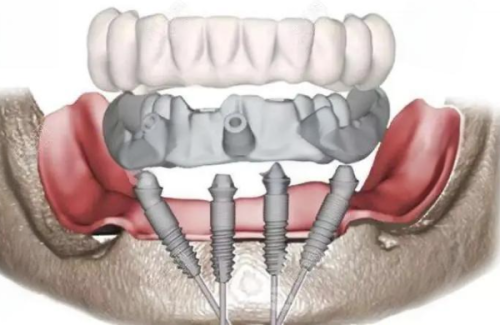

活动义齿一般多少钱一颗费用?2026年最新价格揭秘! 文章揭秘2026年活动义齿最新价格。通常镶活动假牙一颗1000 - 3000元,不同类型费用有别。如隐形义齿1000 - 1200元,便宜但寿命短、咀嚼差;钴铬合金等1500 - 2000元,强度好、使用久;纯钛基托2000 - 3000元,舒适美观。此外,地区、医院等级和医生水平也影响价格,选义齿要综合考量。 活动义齿 2026年03月04日 0 点赞 0 评论 7 浏览

活动义齿哪种最舒服还不伤害基牙?揭秘3种最佳选择! 本文围绕“活动义齿哪种最舒服还不伤害基牙”展开。首先强调了活动义齿舒适与护基牙的重要性,接着介绍了纯钛金属基托活动义齿等三种义齿的特点,包括舒适度、对基牙的影响、价格等。还给出选择建议,要考虑口腔状况、经济因素,并听取医生建议。最后提醒佩戴后注意适应期、清洁和饮食,综合考量选适合自己的义齿。 活动义齿 2026年03月04日 0 点赞 0 评论 12 浏览

补一颗活动义齿多少钱?揭秘真实费用与选择技巧! 本文围绕补一颗活动义齿的费用及选择技巧展开。费用大致在100 - 300元,受材料、修复难易、医院级别、当地经济等因素影响。不同材料义齿各有特点和价格区间。选择时要综合自身情况,选正规机构,多对比。此外,后期维护有成本,需正确佩戴清洁。提醒大家综合考量价格、质量和舒适度,必要时咨询医生。 活动义齿 2026年03月04日 0 点赞 0 评论 7 浏览